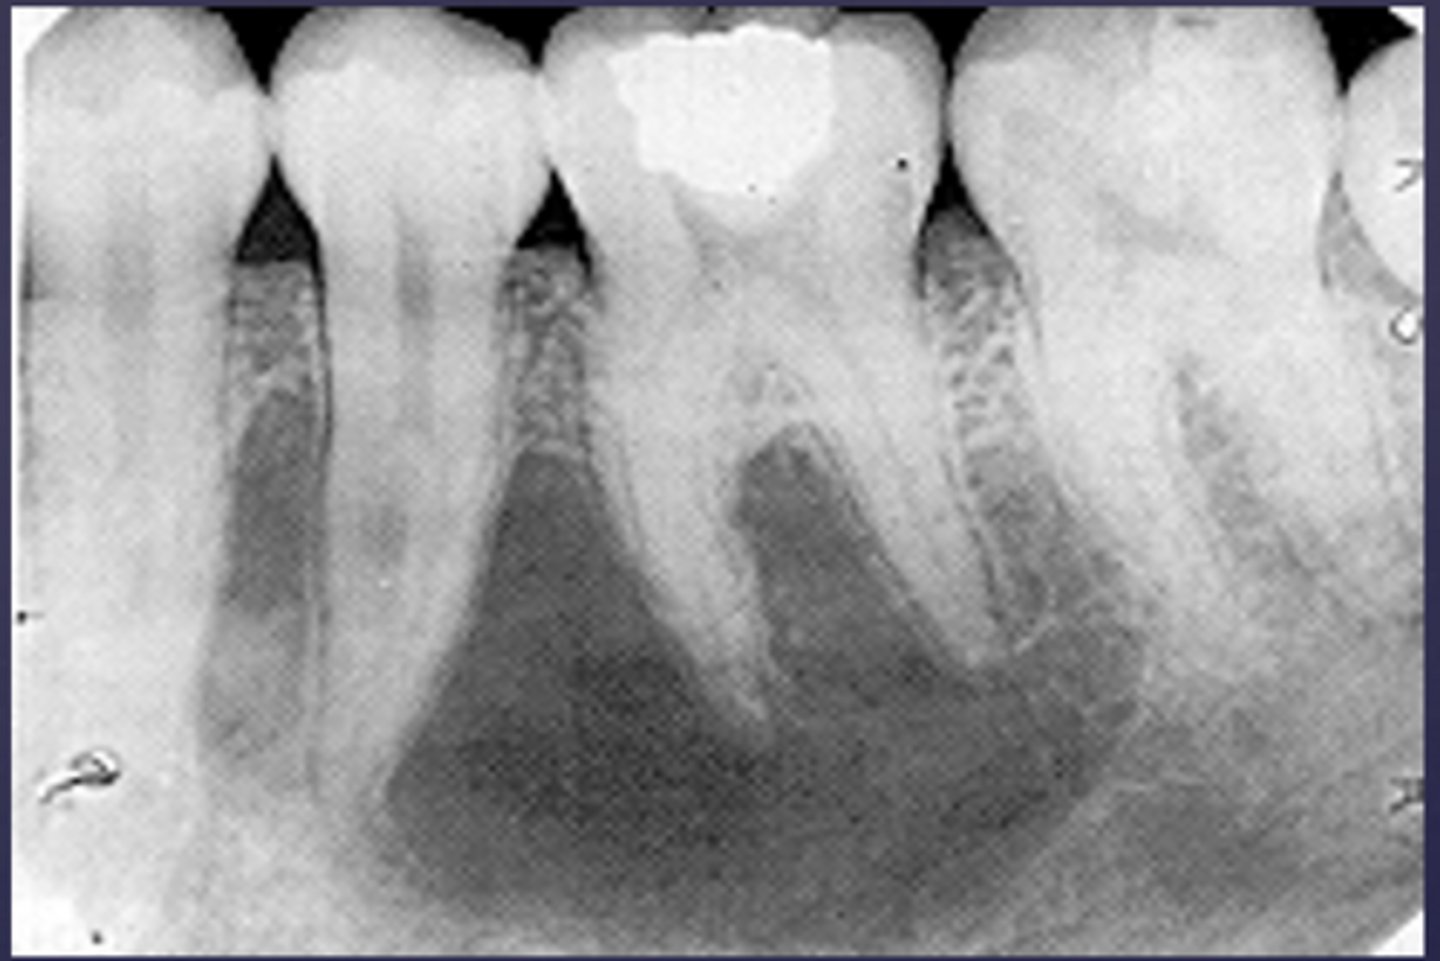

how would you describe this lesion?

A. well-defined, periapical radiolucent lesion associated with #24 and 25

B. ill-defined, periapical radiolucent lesion associated with #24 and 25

C. well- defined, multilocular periapical lesion associated with tooth number 24 and 25

D. mixed density, periapical lesion associated with teeth number 24 and 25

- Also note loss of apical lamina dura of 24, 25

What category would this lesion be part of?

Dysplasia

What would be a differential diagnosis for this lesion?

PCOD (stage 1)

How would you describe the following lesion?

Multiple mixed density periapical target-like entities

The teeth are vital. What category would you put this lesion into?

dysplasia (PCOD)

what could be a differential diagnosis for this lesion?

A. radicular cyst

B. periapical granuloma

C. PCOD (stages 2/3)

D. apical rarefying osteitis